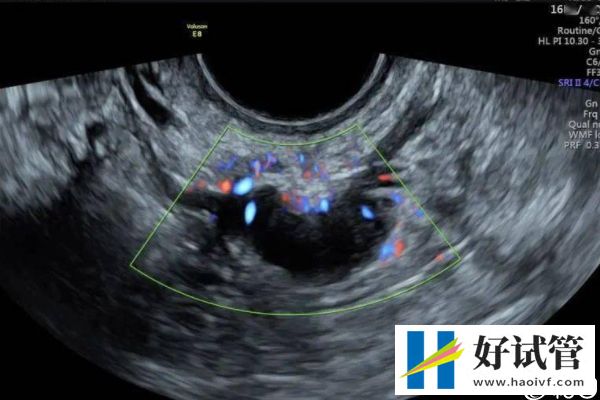

- 取卵后移植前要密切监测自己的内膜情况,相因建议各位要遵医嘱按时到医院做全面检查,如B超检查、激素水平检测等,在子宫内膜环境适宜的情况下,才可以安排胚胎移植手术。如果宫腔环境差,容易造成胚胎着床失败。